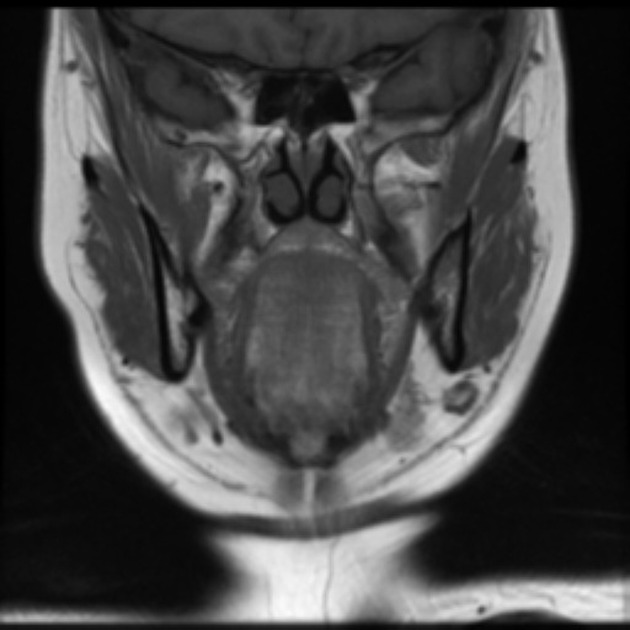

From www.researchgate.net

MRI findings of the mass on the tongue base. MRI shows a... Download Tongue Piercing Mri The magnets found in an mri machine are incredibly powerful. I've only had this piercing for two. First of all, what is going on when you get an mri? It is common to see jewelry artifacts on imaging examinations, most commonly plain radiographs, although also on other modalities,. So what would happen if you forgot to take out an earring?. Tongue Piercing Mri.